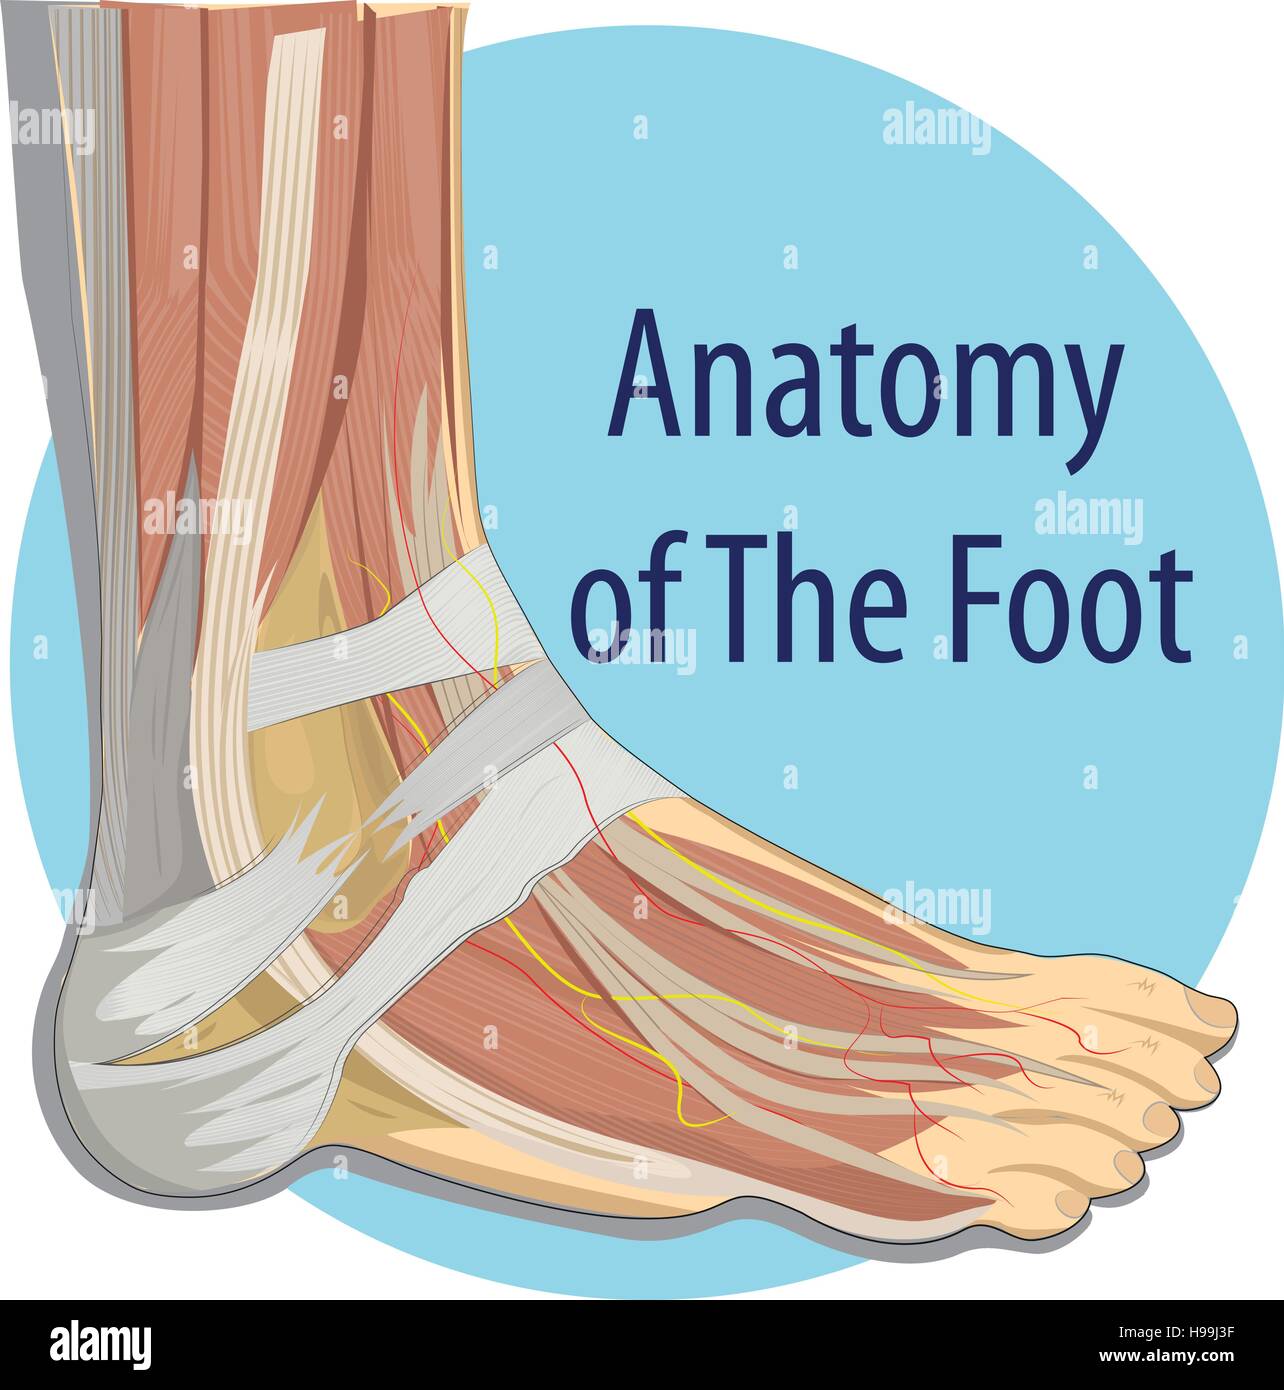

RFTCW7GT–L'articulation de la cheville, les tendons de la cheville anatomie pied eps vector illustration infographie 10

RF2X200ED–L'anatomie de l'articulation de la cheville. Région talocrurale ou os sauteur. Partie du corps humain où le pied et la jambe se rencontrent. Fascia plantaire et tendon d'Achille